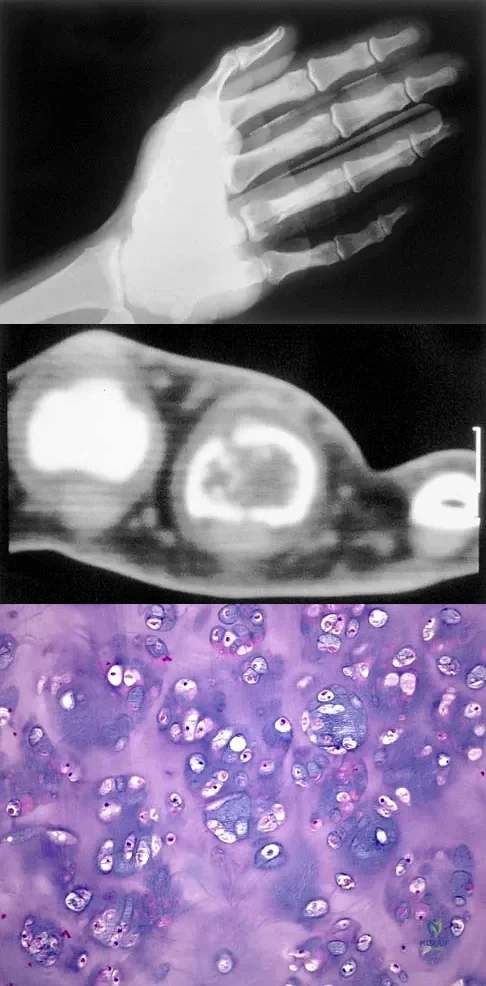

A 30-year-old woman has pain in her right hand. The radiograph, CT scan, and biopsy specimen are seen in Figures 38a through 38c. What is the most likely diagnosis?

Explanation

Question 34

An 83-year-old woman reports pain in her left middle finger after a minor injury. Laboratory studies show a WBC count of 7,000/mm3, an erythrocyte sedimentation rate of 3 mm/h, a uric acid of 10.4 mg/dL, and a normal serum protein electrophoresis. Radiographs are shown in Figures 49a and 49b. A core biopsy specimen is shown is Figure 49c. In addition to treatment of the finger fracture, treatment should include

Explanation